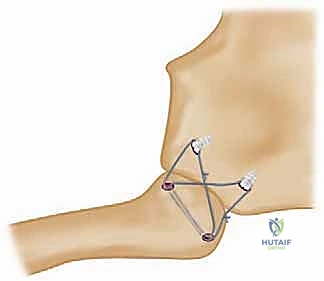

Modern stabilization relies on robust biological reconstruction. While primary repair of the capsule using suture anchors in the manubrium can augment the construct, a figure-of-eight graft reconstruction is the gold standard for restoring multiplanar stability. A semitendinosus or gracilis autograft (or allograft to minimize donor site morbidity) is preferred due to its length and tensile strength.

Drill holes, typically 4.0mm to 4.5mm in diameter, are meticulously created. In the medial clavicle, two holes are drilled from anterior to posterior, approximately 1 cm lateral to the articular margin and 1 cm apart. In the manubrium, two corresponding holes are drilled. Critical Step: When drilling the manubrium and the clavicle, a malleable retractor or a broad periosteal elevator must be placed deep to the bone to protect the mediastinal structures from the drill bit plunging. The drill must always be directed from anterior to posterior, with precise control.

The graft is then passed in a figure-of-eight configuration. Suture passing wires or curved shuttles are used to navigate the graft through the osseous tunnels. The graft is tensioned with the clavicle held in anatomical reduction (often requiring downward and posterior pressure on the medial clavicle). The graft limbs are then sutured to themselves and to the surrounding periosteal tissues using heavy, non-absorbable, braided sutures.

Some modern techniques utilize a "docking" method, where the graft is fixed into blind-ended sockets using biocomposite tenodesis screws, minimizing the need for posterior dissection and reducing the risk to mediastinal structures. Regardless of the specific graft routing, the final construct must be rigidly stable through a functional range of motion on the operating table.